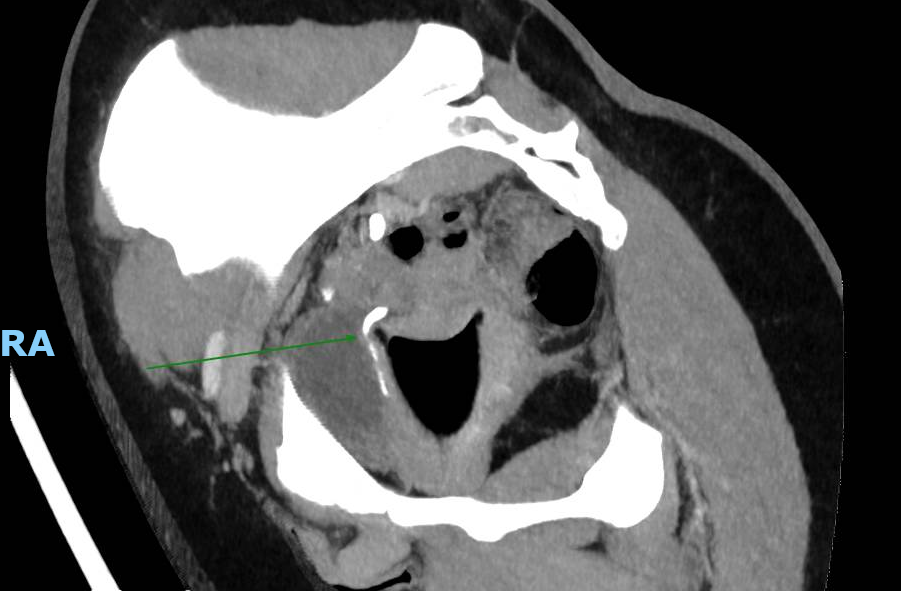

Le CT-scanner réalisé devant une colique néphrétique montre une compression urétérale droite extrinsèque sur une cup menstruelle. Cette dernière est retirée améliorant rapidement les douleurs.

Il existe 5 cas similaires publiés entre 2018 et 2020 (1), tous concernant l’uretère droit. Une étude ex-vivo comparant 14 marques de cup, de tailles et formes différents, a démontré qu’une cup trop grande ou trop rigide pouvait être la cause d’une compression des voies urinaires, en plus d’un inconfort (2).

Ce cas et la littérature qui y est liée démontre l’importance d’exclure la présence d’une cup en cas de colique néphrétique chez les femmes pré-ménopausées.